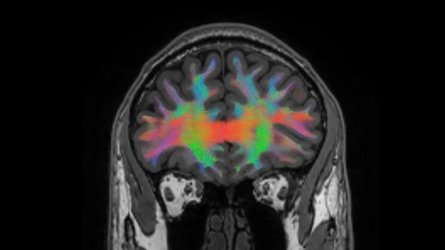

Astronaut brains as beacons for researchers

Brains and cells